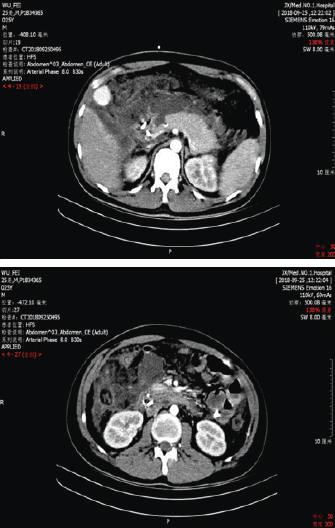

急性胰腺炎ct图片图解

急性胰腺炎ct图片图解,急性胰腺炎ct图片

多排螺旋ct在急性胰腺炎中的应用价值

急性胰腺炎ct图片

急性胰腺炎ct

胰腺炎ct表现

胰腺炎ct图片

急性胰腺炎ct影像表现

胰腺炎ct